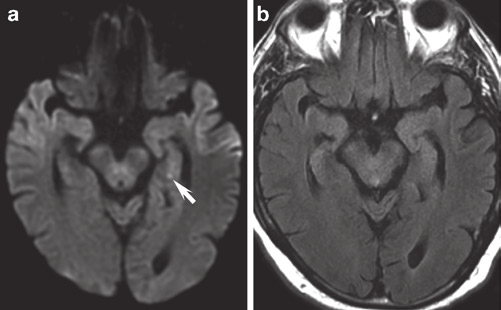

神経内科の専門医、ピョン・ジアシオン博士は「脳機能自体は正常で、一時的に記憶を失ったもの」と説明しました。

続いて「”一過性全健忘”の一種で脳の血流量が低下し、脳に十分な酸素が供給されなかったことが原因である」と付け加えました。

一度一過性全健忘を経験した患者は、脳卒中の発症リスクが30%高いことから、簡単に済む問題ではありません。